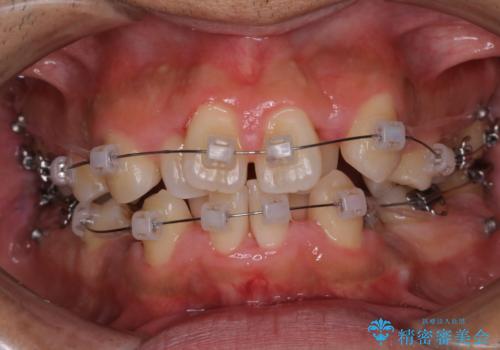

表のワイヤー装置で矯正中にPMTCで綺麗にお掃除

担当医 歯科衛生士